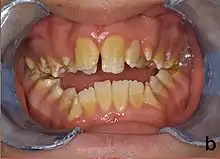

Amelogenesis imperfecta, hypoplastic type. Note the association of pitted enamel and open bite.